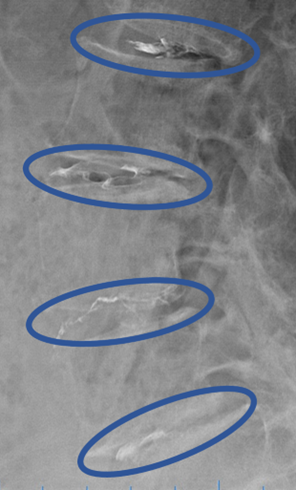

患者様と相談の元、L1/2、2/3、3/4、4/5にセルゲル法を施行

DiscoGelを入れた後の画像になります。

治療は 30分程度で終了

回復室で休憩後、歩いて帰院されました。